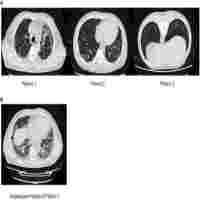

| Abstract | This report describes the case of a 41-year-old male patient complaining of a hacking cough. The patient was treated with a Janus kinase (JAK) inhibitor for psoriasis. Blood tests revealed mild lymphopenia and high levels of serum cryptococcal antigen. Chest computed tomography revealed infection in the lower lobe of the left lung. Metagenomic next-generation sequencing of bronchoalveolar lavage fluid revealed Tropheryma whipplei. Tropheryma whipplei and Cryptococcus antimicrobial therapies were sequentially administered. During follow-up, the patient showed clinical and radiographic improvement. Tropheryma whipplei is an opportunistic Gram-positive rod-shaped bacterium belonging to the family Actinomycetes. Lung involvement is an unusual but classic manifestation of Whipple’s disease. This is the first report of pneumonia caused by infection with Tropheryma whipplei complicated by Cryptococcus. To our knowledge, this is the first case report of Tropheryma whipplei infection following the use of JAK inhibitors. Clinicians should be aware of opportunistic infections that can occur during treatment with JAK inhibitors. |